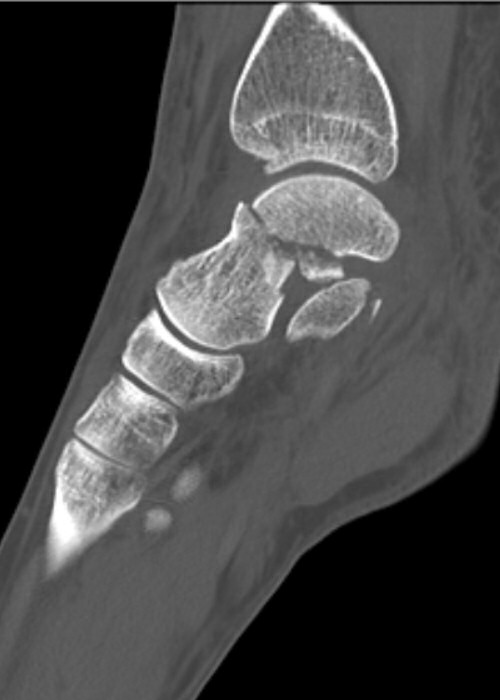

Slätröntgen vid misstanke om skelettskada i foten, DT krävs för att kartlägga fraktur i talus [1].

Skada: Fraktur talus